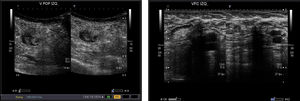

El estudio venoso con eco-doppler o dúplex es la prueba de imagen de elección para el diagnóstico de la TVS (fig. 2).

Confirma de manera objetiva el diagnóstico clínico y permite realizar el diagnóstico diferencial. La falta de compresibilidad de la vena o la obstrucción al flujo son los criterios ecográficos diagnósticos de la trombosis.